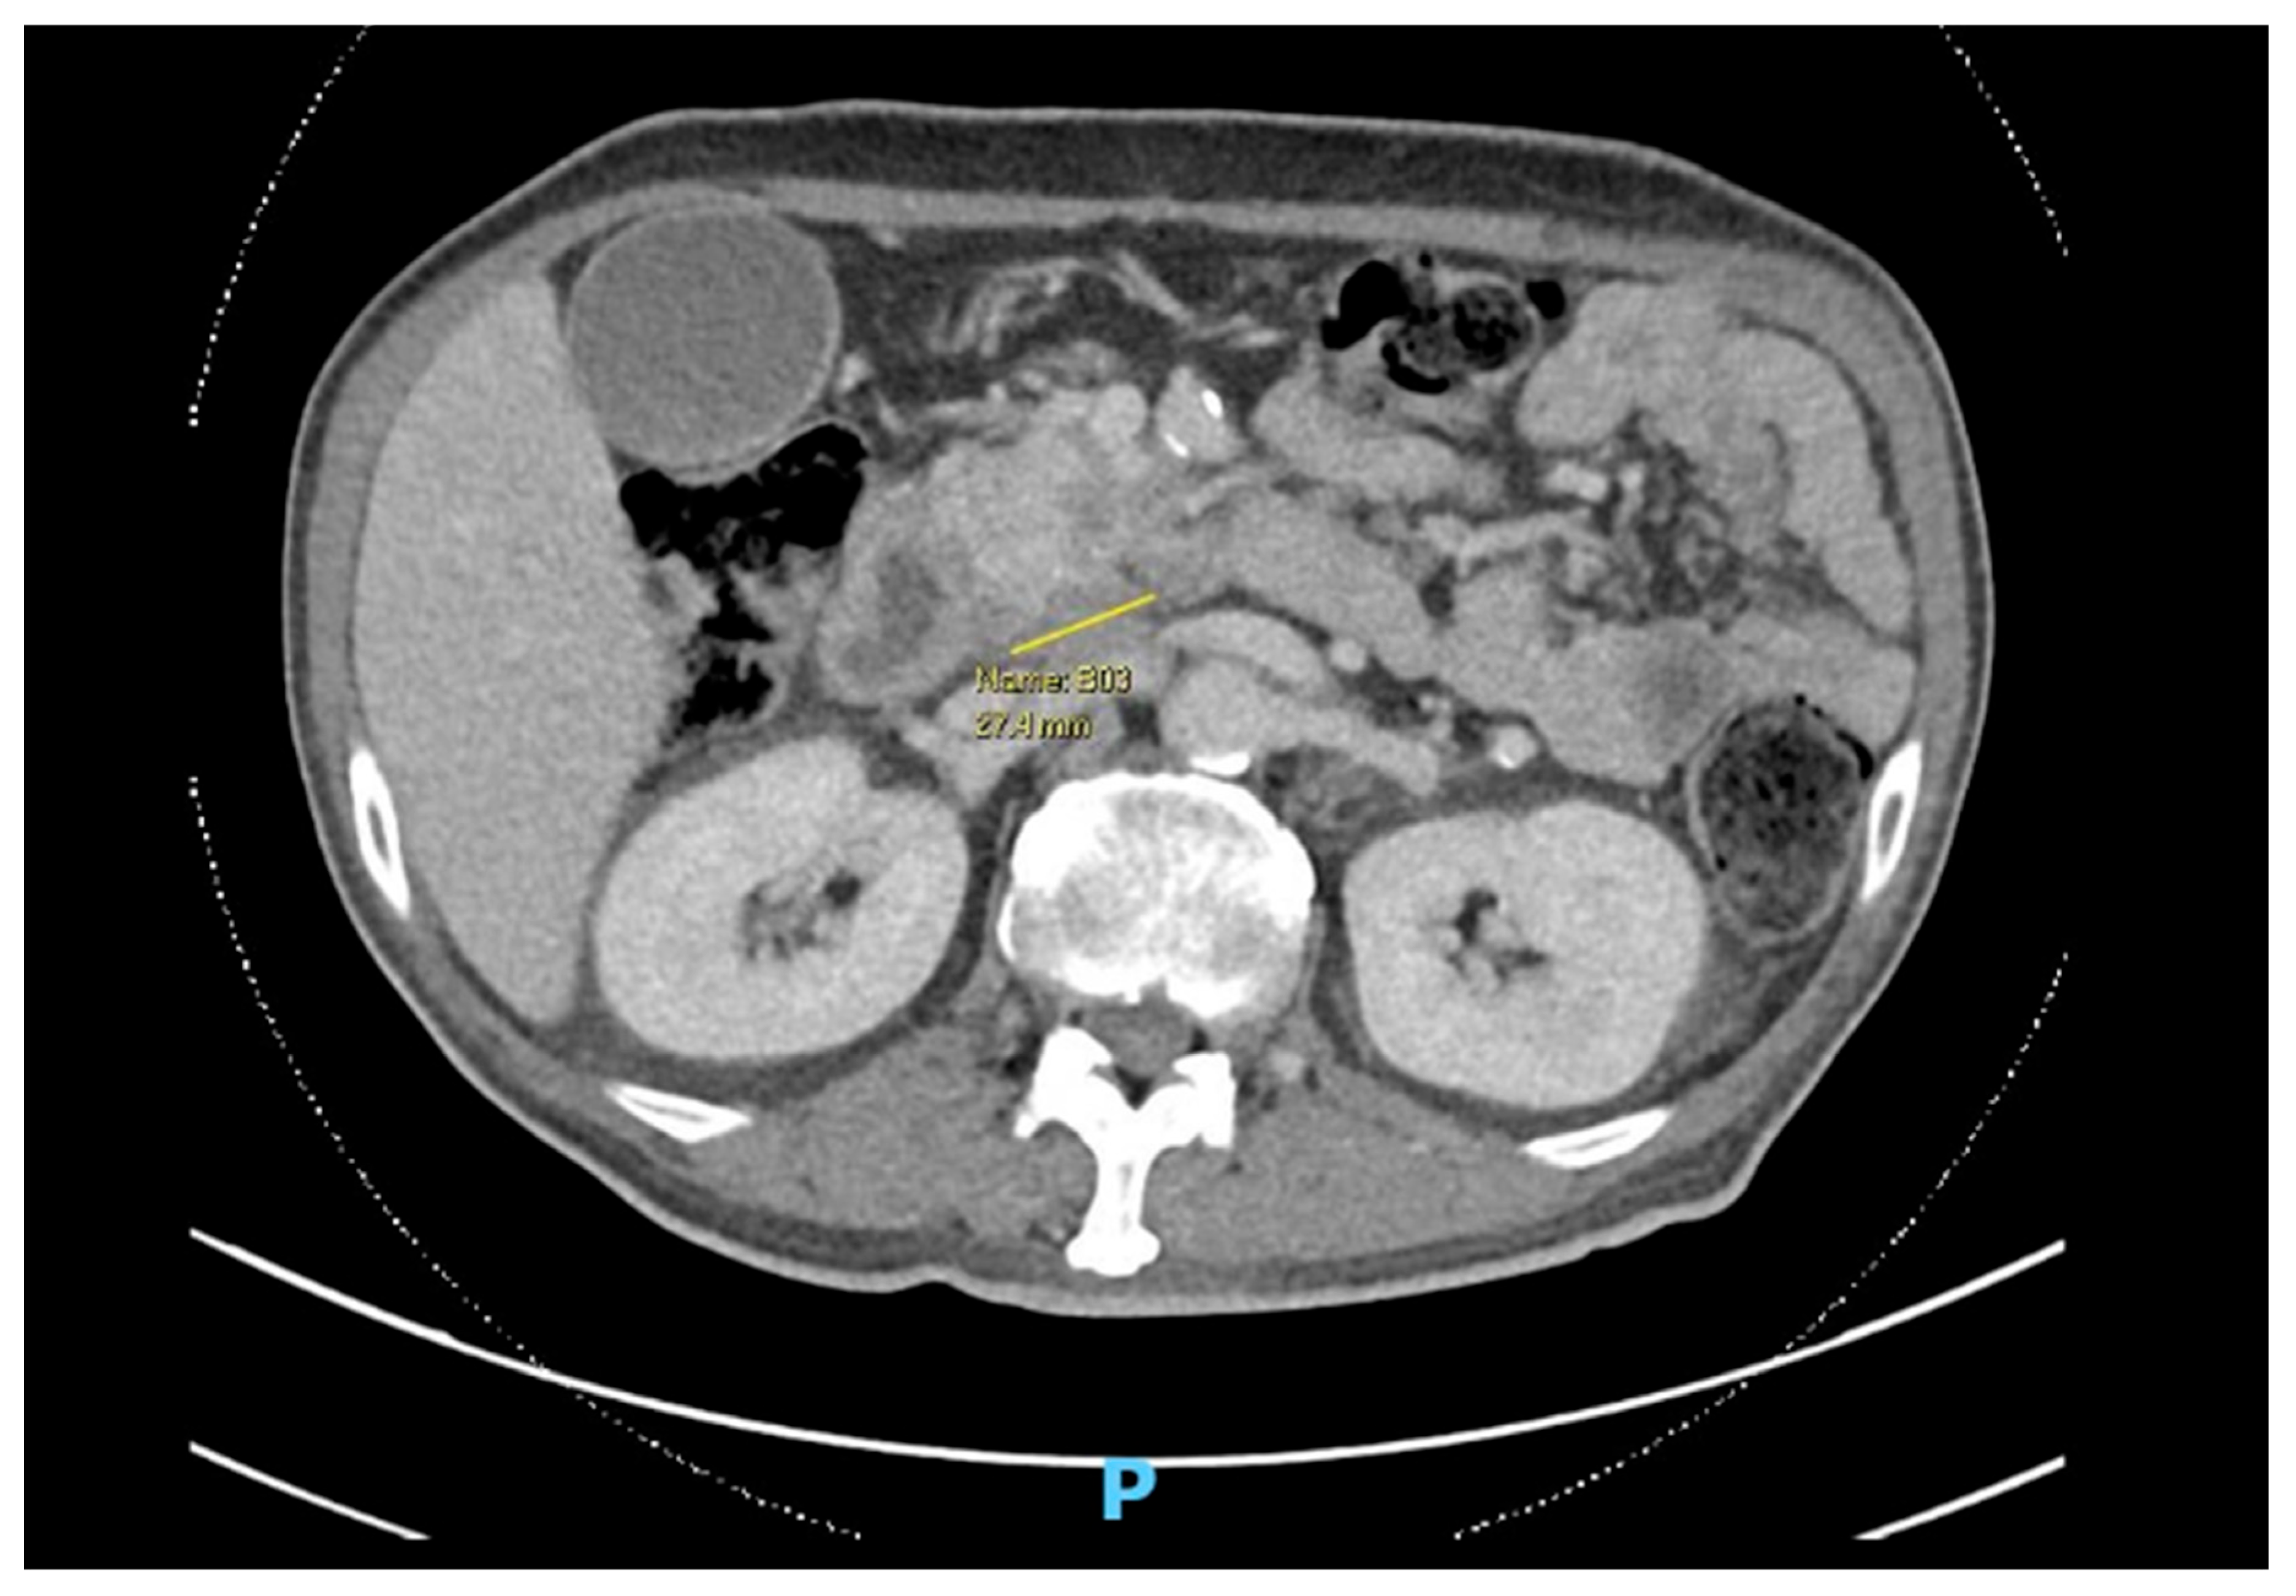

Patient A is a 60-year-old male, a driver and smoker, with poorly controlled diabetes, chronic kidney disease (CKD), and ischemic heart disease (IHD), newly diagnosed with a locally advanced, borderline resectable head of pancreas malignancy with superior mesenteric vessel involvement (Figure 1).

Figure 1. Computed Tomography (CT) scan showing axial cut of pancreatic malignancy.